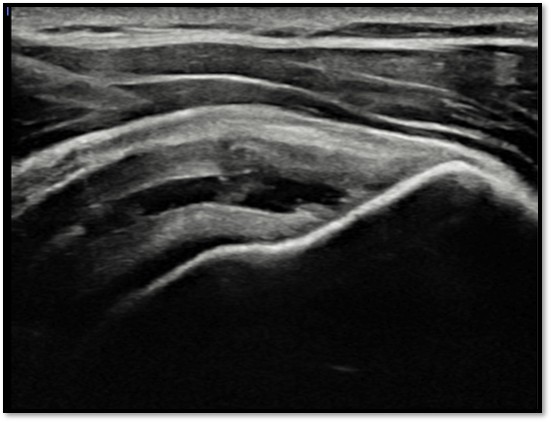

케이스 2: 점액낭면측 파열 → 리제네텐

환자: 38세 여성, 필라테스 강사

진단:

MRI: 극상건 점액낭면측 부분파열 (약 35%)

인대 얇아짐 소견

치료:

리제네텐 콜라겐 패치 적용

재생주사 병행

결과:

16주 후 MRI: 인대 두께 증가 확인

필라테스 강의 복귀

Q4. 제 파열이 어느 쪽인지 어떻게 알 수 있나요?

MRI 또는 초음파 검사로 확인할 수 있습니다. 단, 영상 판독은 전문성이 필요합니다. 플래티넘의원에서는 MRI를 직접 재검토하고, 초음파로 실시간 확인하여 정확한 위치와 양상을 진단합니다.